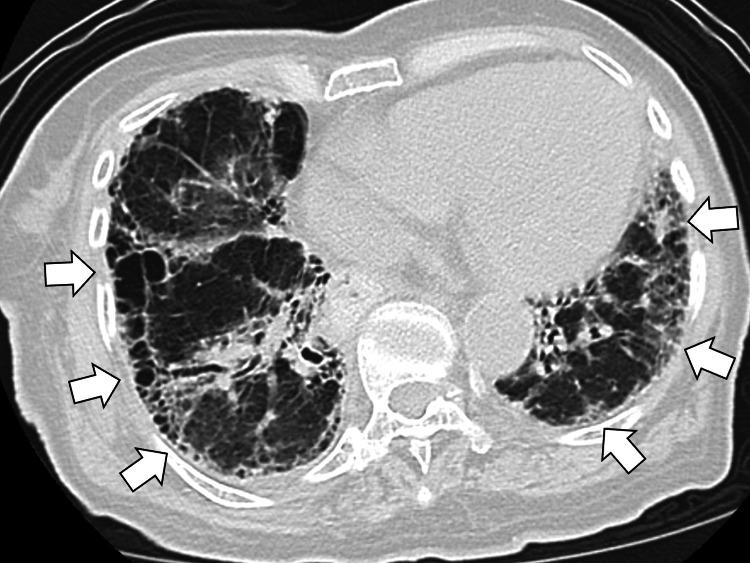

This case report describes a 95-year-old woman with a history of cardiovascular and gastrointestinal diseases who presented with fever and anorexia. She was diagnosed with influenza A and secondary bacterial pneumonia. Despite antiviral and antibiotic treatment, her respiratory condition worsened. Detailed examination revealed characteristic joint deformities, elevated rheumatoid factor, and anti-cyclic citrullinated peptide antibodies. Imaging showed interstitial pneumonia and paradoxical breathing with elevation of the membranous portion of the trachea, indicating tracheomalacia. The patient was diagnosed with previously unrecognized rheumatoid arthritis with associated interstitial pneumonia and tracheomalacia. Immunosuppressive therapy with prednisolone and azathioprine improved her condition. This case highlights the importance of thorough systemic evaluation in elderly patients with unexplained respiratory symptoms and the need to consider late-onset autoimmune diseases, including rheumatoid arthritis, in the differential diagnosis.

摘要